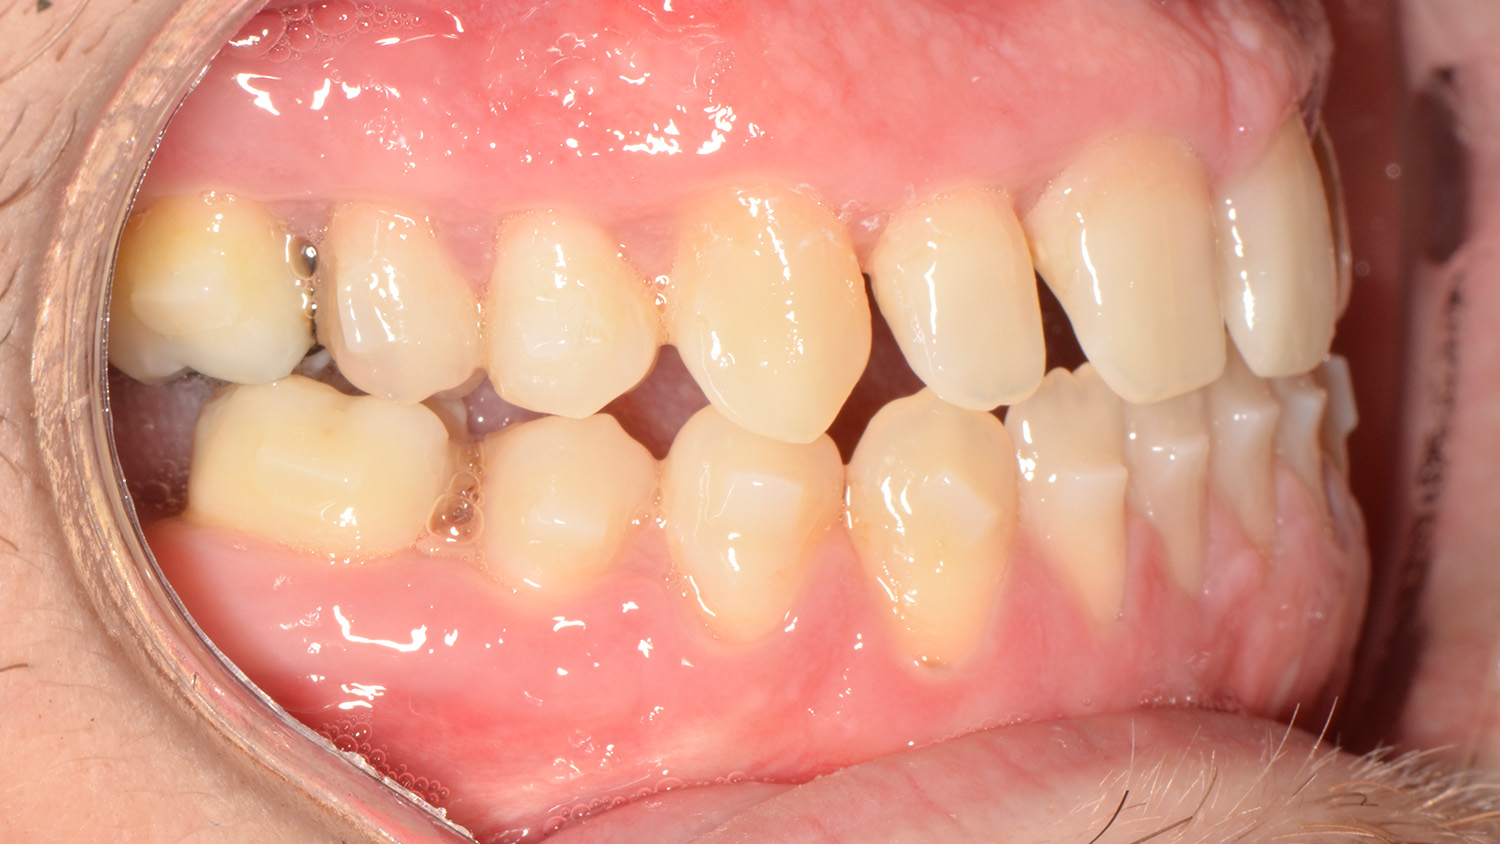

Intraoral examination showed an Angle Class III relationship on both sides, along with an anterior open bite. Additionally, a narrow maxilla with a bilateral posterior crossbite was observed.

As shown in the accompanying images, the planned vertical correction was fully achieved. At this stage, provisional composite veneers were placed from canine to canine in the upper arch to enhance the patient’s aesthetics and compensate for Bolton’s discrepancy.

For sagittal correction, a new set of aligners made from Trugen XR™ material was fabricated. The corono-distal tipping of the premolars in the fourth quadrant was corrected using intermaxillary elastics.

Treatment results

Ultimately, we successfully corrected the crossbite, open bite, and Class III canine relationship. The patient rehabilitated tooth #26 with an on lay and tooth #47 with an implant, resulting in a stable occlusion. Post-treatment retention involved a fixed retainer in the lower arch and removable retainers for both upper and lower arches to maintain the treatment results.